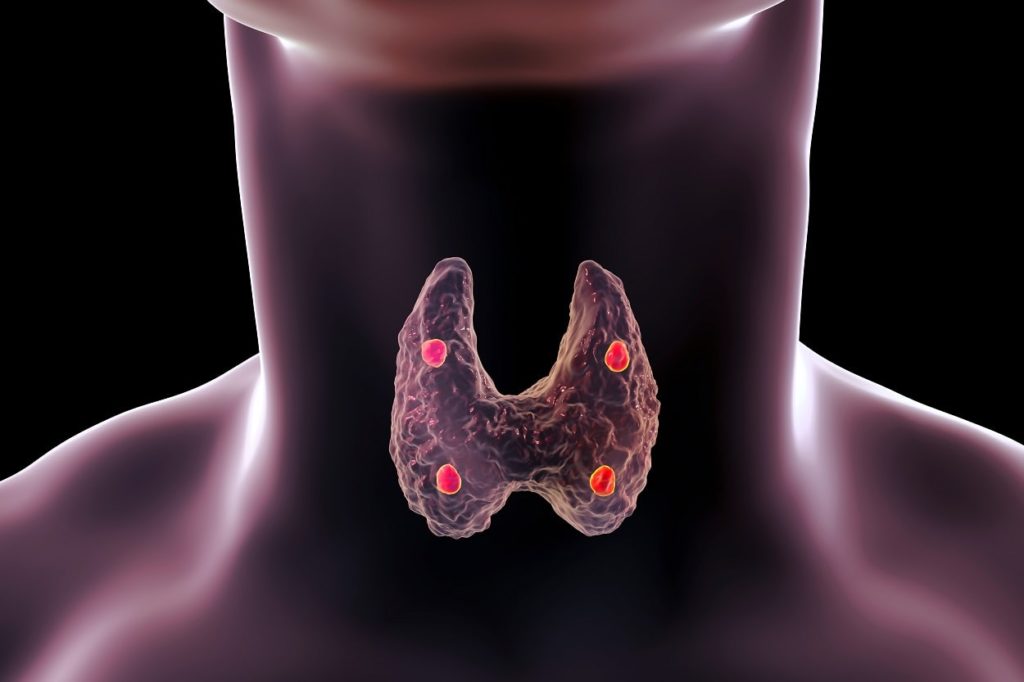

Estas glándulas se encargan principalmente de la liberación de hormonas, las cuales son distribuidas hacia los distintos órganos “diana”. Las glándulas endocrinas más importantes del cuerpo son las glándulas suprarrenales o adrenales, la hipófisis, la tiroides, la paratiroides y la glándula pineal, los ovarios, la placenta y los testículos.

– La tiroides se encuentra en el cuello y participa de la secreción de la hormona tiroxina, triyodotironina y calcitonina, que también influyen sobre el metabolismo.

La característica principal de las glándulas endocrinas es que sus células están organizadas en forma de “cordones” o folículos.

Las glándulas con organización interna tipo cordón son las más comunes y se distinguen por el hecho de que sus células se “apilan” alrededor de capilares sanguíneos, hacia los que liberan sus productos cuando el estímulo adecuado las alcanza.

En las glándulas endocrinas con organización tipo folículo, las células responsables de la secreción forman una especie de cavidad hacia la que vierten las hormonas que producen. Las hormonas permanecen en dicha cavidad hasta que llega el estímulo adecuado y subsecuentemente se reabsorben para pasar hacia los vasos y capilares sanguíneos.